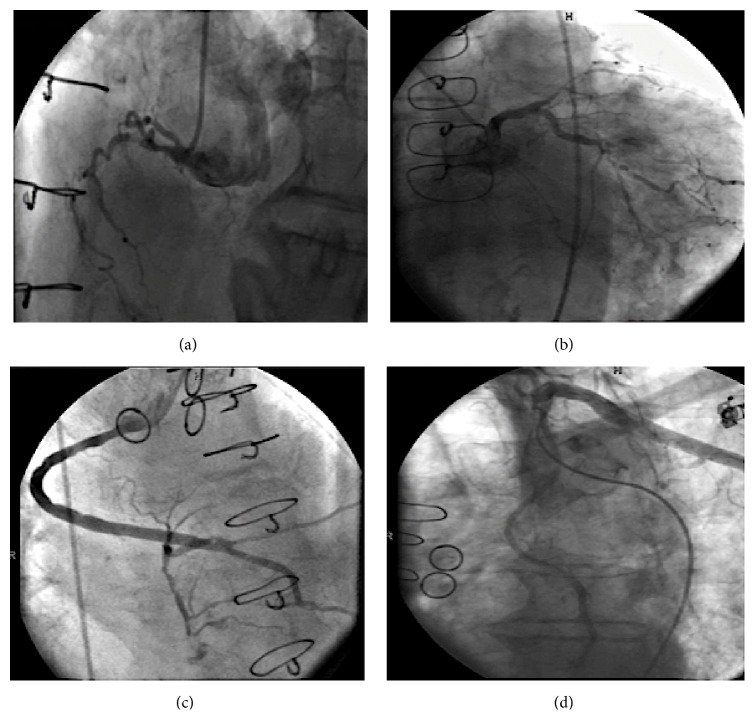

Given extensive prior cardiac history, “anginal equivalent” symptoms, ischemic ECG changes, and elevated troponin I levels, non-ST elevation myocardial infarction (NSTEMI) was diagnosed and patient was started on appropriate optimal medical therapy for acute coronary syndrome. Subsequently, patient underwent an early invasive strategy of cardiac catheterization and angiography that revealed chronic, severe, native 3-vessel CAD (Figures 1(a) and 1(b)). He had patent sequential saphenous venous graft to right posterolateral and posterior descending artery and a patent left internal mammary artery to left anterior descending artery (Figures 1(c) and 1(d)). The saphenous venous grafts to the diagonal and circumflex artery were chronically occluded with evidence of collaterals. Based on the coronary anatomy the patient was managed conservatively with optimal medical therapy with no plan for percutaneous intervention or revascularization.

Figure 1.

(a) Right coronary artery 100% occluded in the proximal segment. (b) Left anterior descending with 99% ostial and 100% mid occlusion and circumflex 99% distal occlusion. (c) Sequential vein graft to right posterolateral and posterior descending artery with 40% proximal disease. (d) Left internal mammary artery graft to distal left anterior descending widely patent.